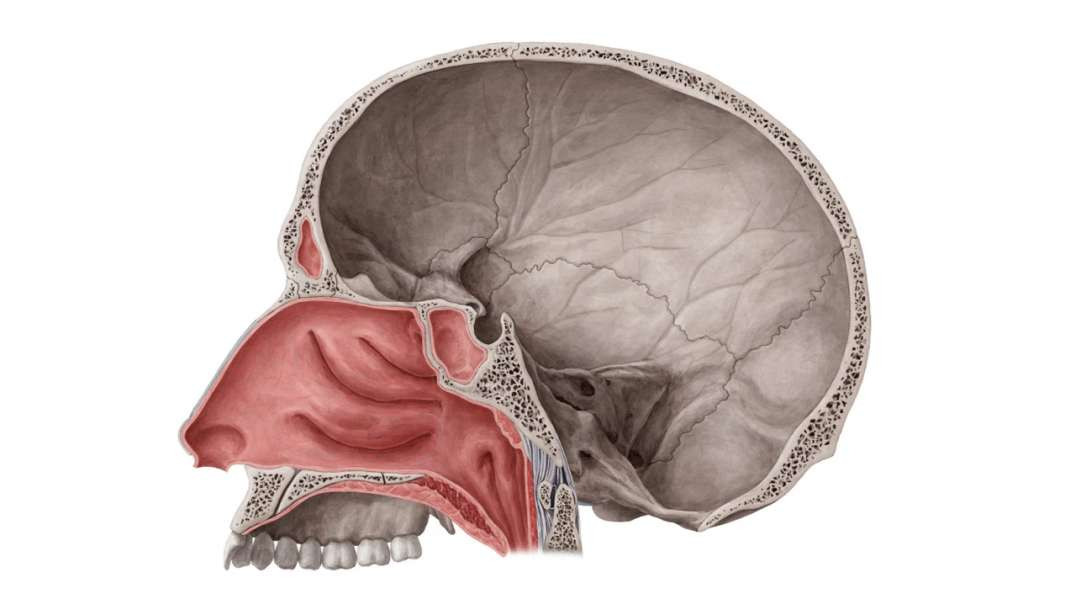

Armando - Clinical Anatomy - Nasal Cavity and Sinuses

Armando - Clinical Anatomy - Nasal Cavity and Sinuses